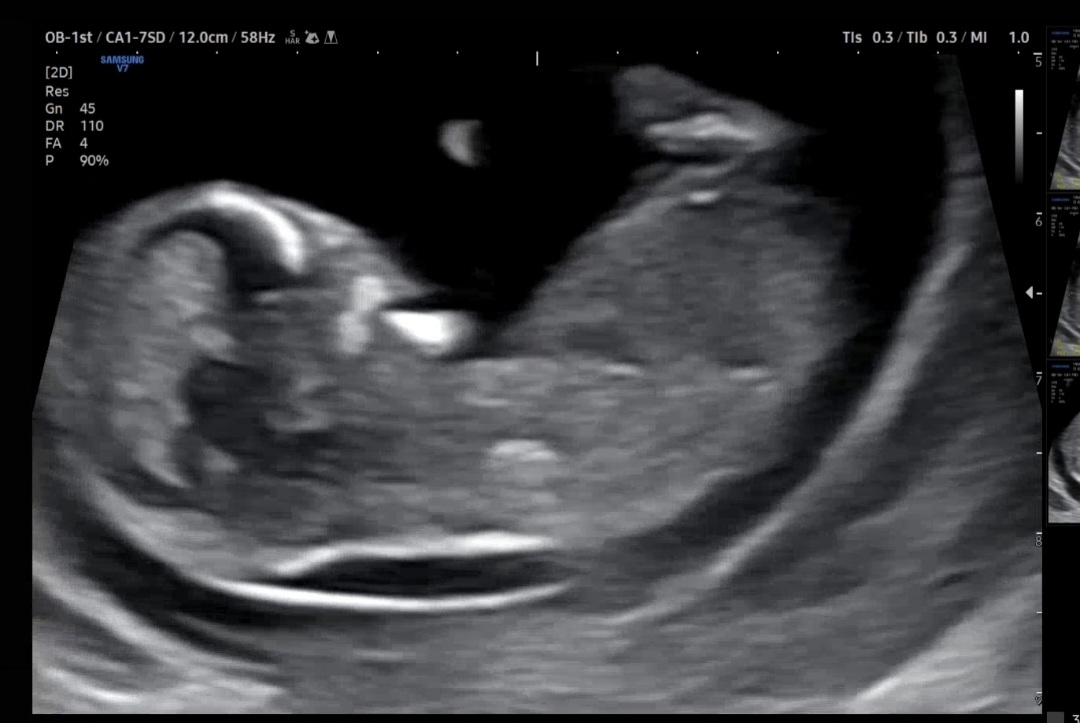

기형아 검사는 다음주 12주 6일차로 볼건데 서브병원에 11주 6일에 다녀왔는데 목투명대가 두꺼워 보여서요 ㅠㅠ 의사쌤은 목투명대 얘기는 없고 코뼈랑 턱라인이 이제 보이죠? 이런말만 하셔서 잘모르겠어요! 혹시 밑에 잘 보이는 게 목투명대가 아니라 양막일 수도 있나요?